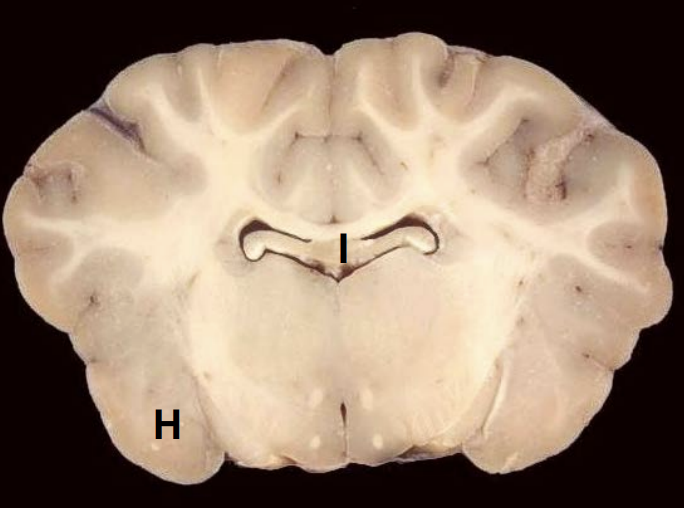

H

Amygdala

I

Body of fornix